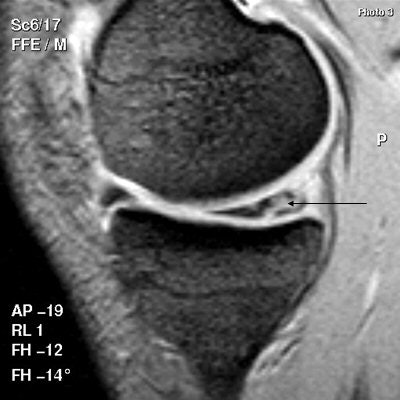

| Above, scan shows a tear extending into the undersurface of the posterior horn of the medial meniscus. Below, patient has a torn anterior cruciate ligament (ACL), shown as discontinuity toward the upper end of the ligament, along with swelling of the lower part. All images courtesy of Dr. Stephen Brearley. |